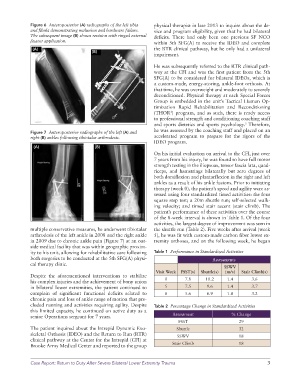

Figure 7 Anteroposterior radiographs of the left (A) and he was assessed by the coaching staff and placed on an

right (B) ankles following tibiotalar arthrodesis. accelerated program to prepare for the rigors of the

multiple conservative measures, he underwent tibiotalar the shuttle run (Table 2). Five weeks after arrival (week

arthrodesis of the left ankle in 2008 and the right ankle 5), he was fit with custommade carbon fiber lower ex

in 2009 due to chronic ankle pain (Figure 7) at an out tremity orthoses, and on the following week, he began